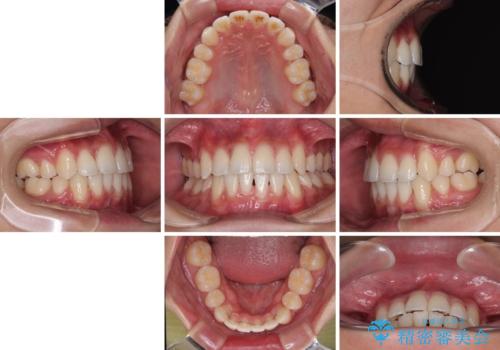

患者様の望んでいた通りの歯列や口元に仕上げることができました。